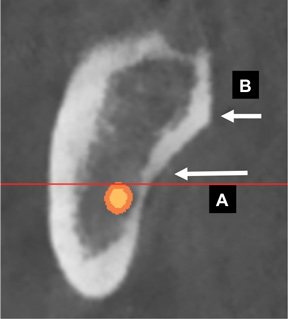

Fig 24. Turbinate bones: cross-sectional view. They are found within the nose. There is an inferior (A), middle (B), and superior turbinate (C).

Figure 24